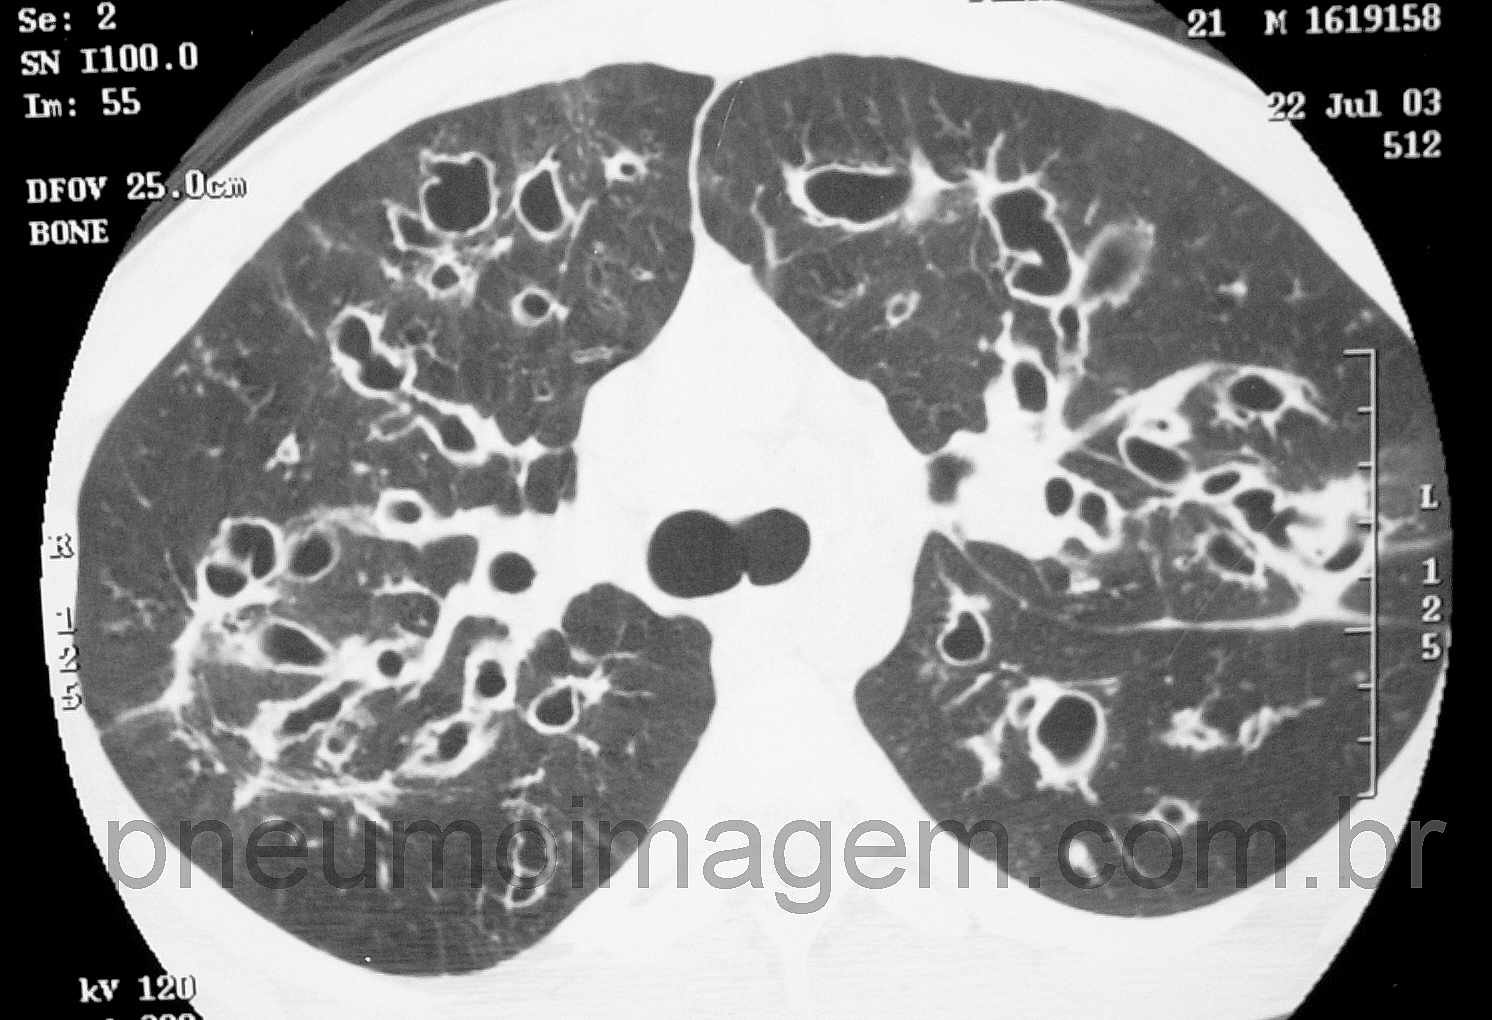

DIRETRIZES BRASILEIRAS DE DIAGNÓSTICO E TRATAMENTO DA FIBROSE CÍSTICA: FAÇA O DOWNLOADA fibrose cística (FC) é uma doença genética autossômica recessiva caracterizada pela disfunção do gene CFTR. Trata-se de uma doença multissistêmica que ocorre mais frequentemente em populações descendentes de caucasianos. Nas últimas décadas, diversos avanços no diagnóstico e tratamento da FC mudaram drasticamente o cenário dessa doença, com aumento expressivo da sobrevida e qualidade de vida.